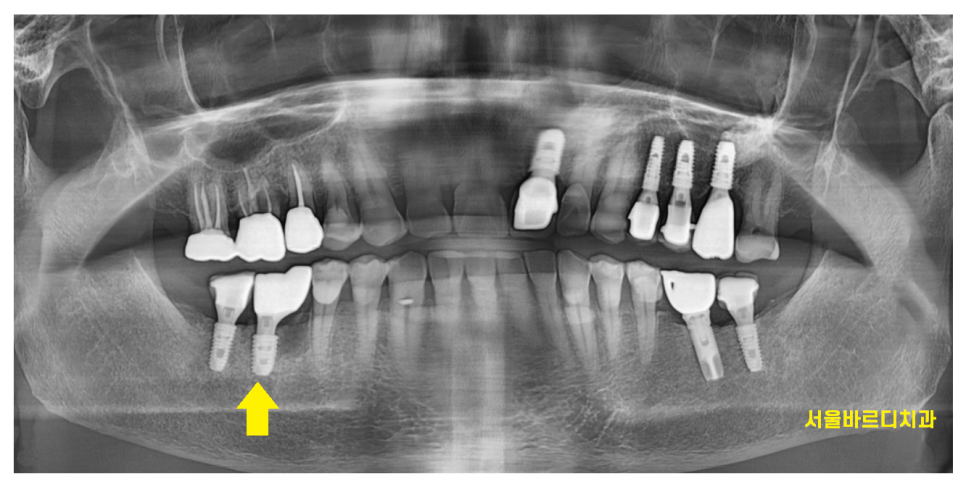

24.05.03

암사동 임플란트 체크만 하러 오셨다가

바로 머리를 만드는 작업을 진행

24.05.23

암사동 임플란트 완성해드렸습니다.

딱딱한 음식은 절대 피하셔야한다.

당부를 드리면서

치료를 마무리 해드렸는데요.